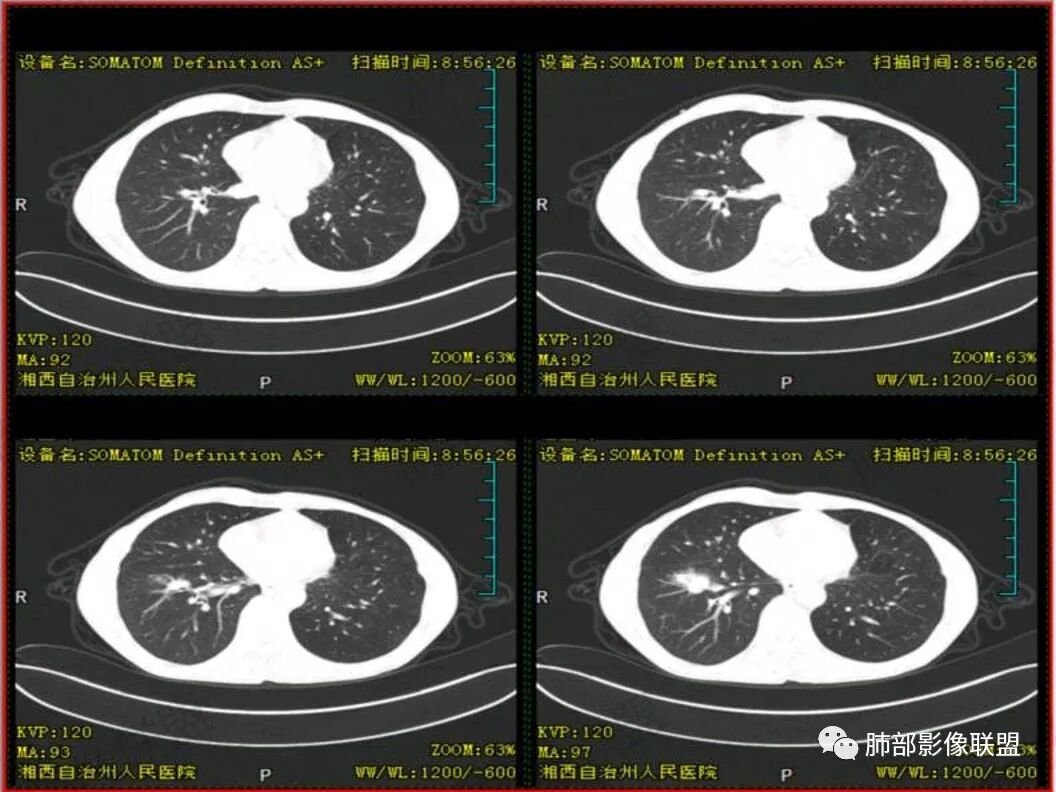

双上肺多发斑片、结节及条索影,边缘清晰,右肺下叶肿块,边缘分叶毛刺,密度不均有坏死,叶间胸膜及侧胸膜牵拉凹陷,斜裂可见六个核桃,周围小叶间隔呈串珠状,纵膈淋巴结肿大坏死,边缘可见钙化,考虑双肺结核,右下肺腺癌。鉴别鳞癌。

胸CT可见右肺下叶前基底段占位性病变,病灶周围可见周围不清毛玻璃影,病灶边缘可见分叶,呈膨胀性生长,纵隔窗可见病灶内呈偏心性坏死,增强扫描静脉期强于动脉期,纵隔隆突下淋巴结可见肿大坏死。

双上肺多发病灶,考虑结核(陈旧灶为主),右肺下叶前基底段占位,分叶、毛刺、胸膜牵拉,中央坏死,局部壁不光滑,前基底段支气管未见显示,不均匀强化,病灶远端阻塞性炎症,纵隔淋巴结肿大、融合。综合考虑恶性病变,鳞癌可能大。

双上肺多发条索及斑片状,局部支气管扩张,考虑结核。右下肺病灶分叶毛刺,胸膜牵拉,不均匀强化,坏死。纵隔淋巴结肿大,坏死,考虑右下肺肺癌并淋巴结转移,鳞癌可能。

影像表现为 双肺上叶多发索条斑片影,可见支气管牵拉性扩张,考虑为陈旧肺结核纤维硬结灶。右肺下叶前基底段团块影膨隆生长,边界不清,呈分叶,毛刺,胸膜牵拉,支气管截断,中央区坏死明显,但未形成空洞,坏死区边缘光整,不均匀环形强化,隐约见壁结节。纵隔淋巴结肿大伴钙化,病灶远端见阻塞性炎症,结合CYFRA21-1偏高,应想到考虑恶性病变,鳞癌可能性大。